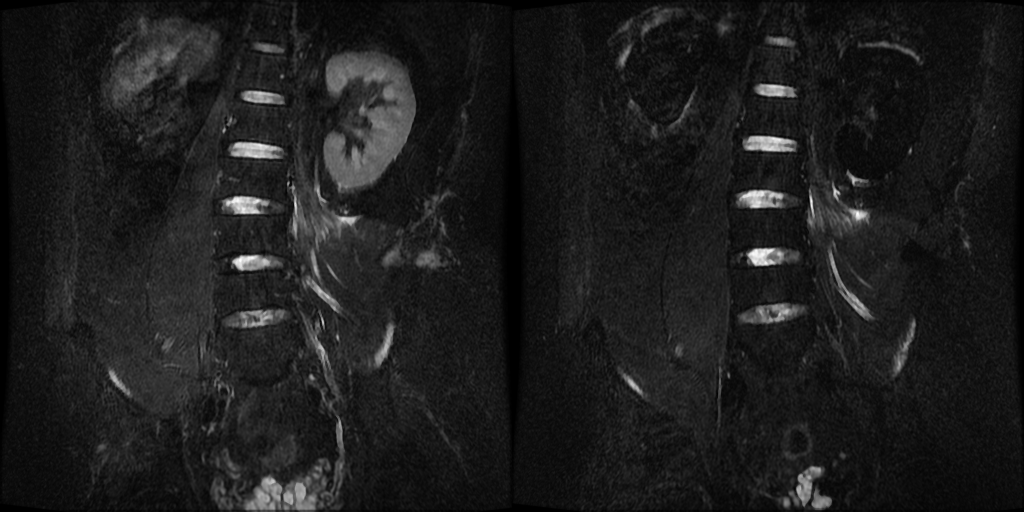

- 挑出source_domain和target_domain的3D数据(这部分可以跟医生核实,例如,在作者的项目中,发现转换后的.nii.gz文件包含关键词"Cor"&"CubeSTIR"&"src",据此选出打药前后的被试数据)